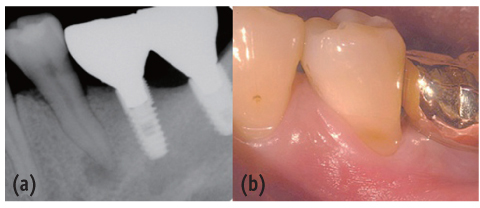

Figure 2

Preoperative panorama view. Periapical radiolucency was observed at the apex of mandibular left second premolar.

Figure 2 Preoperative panorama view. Periapical radiolucency was observed at the apex of mandibular left second premolar.